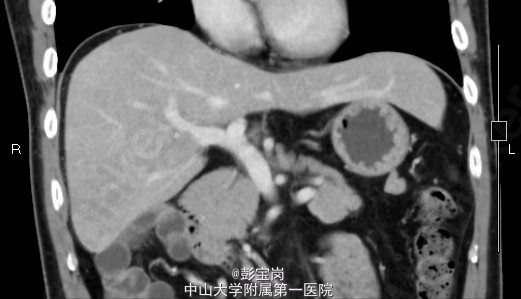

男性,42岁;因“肝癌行TACE术后,拟行手术治疗”入院。患者1月前体检发现原发性肝癌,于25天前在外院行肝动脉栓塞化疗(TACE)术。2天前患者就诊我院,查上腹CT示:右肝后叶多发结节或肿块,碘油栓塞后改变,病灶内和周边部仍有血供,门脉右后下支癌栓形成。现为进一步诊治门诊拟“肝细胞癌”收住我科。起病以来,精神食欲可,大小便通畅,体重无明显变化。既往史肾结石病史,否认肝炎病史。

查体无特殊; 检验:白细胞WBC:13.27;血红蛋白Hb:121g/L;血小板PLT:225x10^9/L;肿瘤标记物:甲胎蛋白(AFP)111.32 ug/L;癌胚抗原(CEA)9.40 ug/L;CA125 20.2 U/mL;CA19-9 11.04 U/L;HBsAg(+)

诊断:肝细胞癌 处理:右半肝切除术、胆囊切除术、腹腔粘连松解、膈肌部分切除修补、门静脉切除取癌栓、右侧肾上腺转移瘤切除